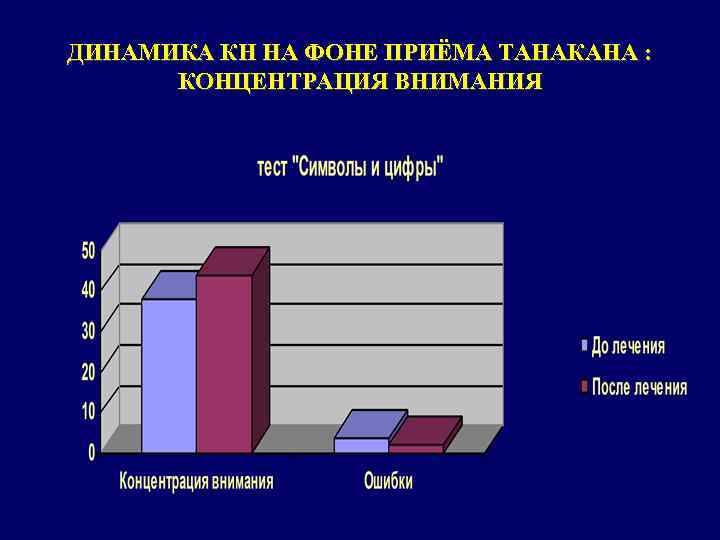

ДИНАМИКА КН НА ФОНЕ ПРИЁМА ТАНАКАНА : КОНЦЕНТРАЦИЯ ВНИМАНИЯ